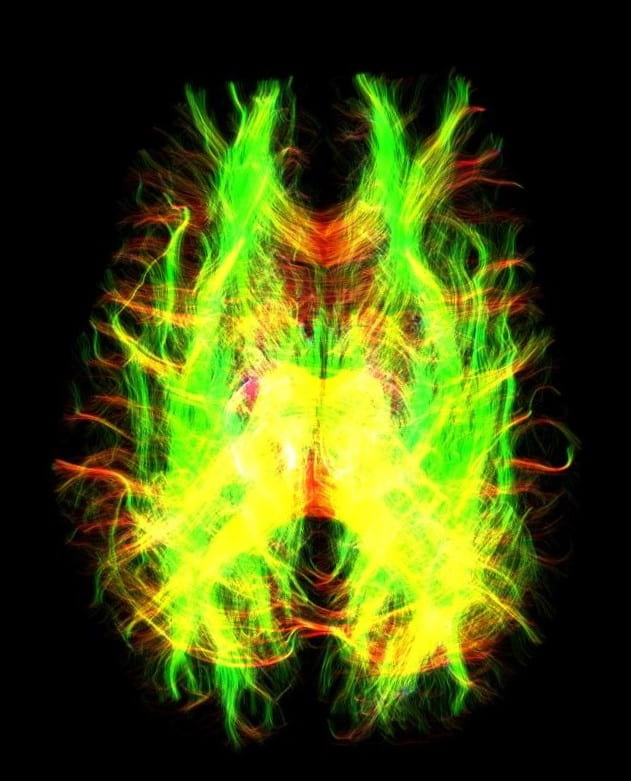

Imaging Capabilities With our brand-new General Electric 3.0 Tesla MRI Scanner, the suite is capable of performing a host of imaging analysis including the following: Site Menu Menu Icon of three lines stacked on top of eachother Sidebar Menu Chev Down Icon of hollow arrow pointing down Arrow Left Icon of arrow pointing left Neurotechnology Suite Chev Up Icon of hollow arrow pointing up Imaging Capabilities CONTACT Location: 50 Prescott Street (Gateway Park II) practicepoint@wpi.edu LinkedIn Icon of LinkedIn Logo